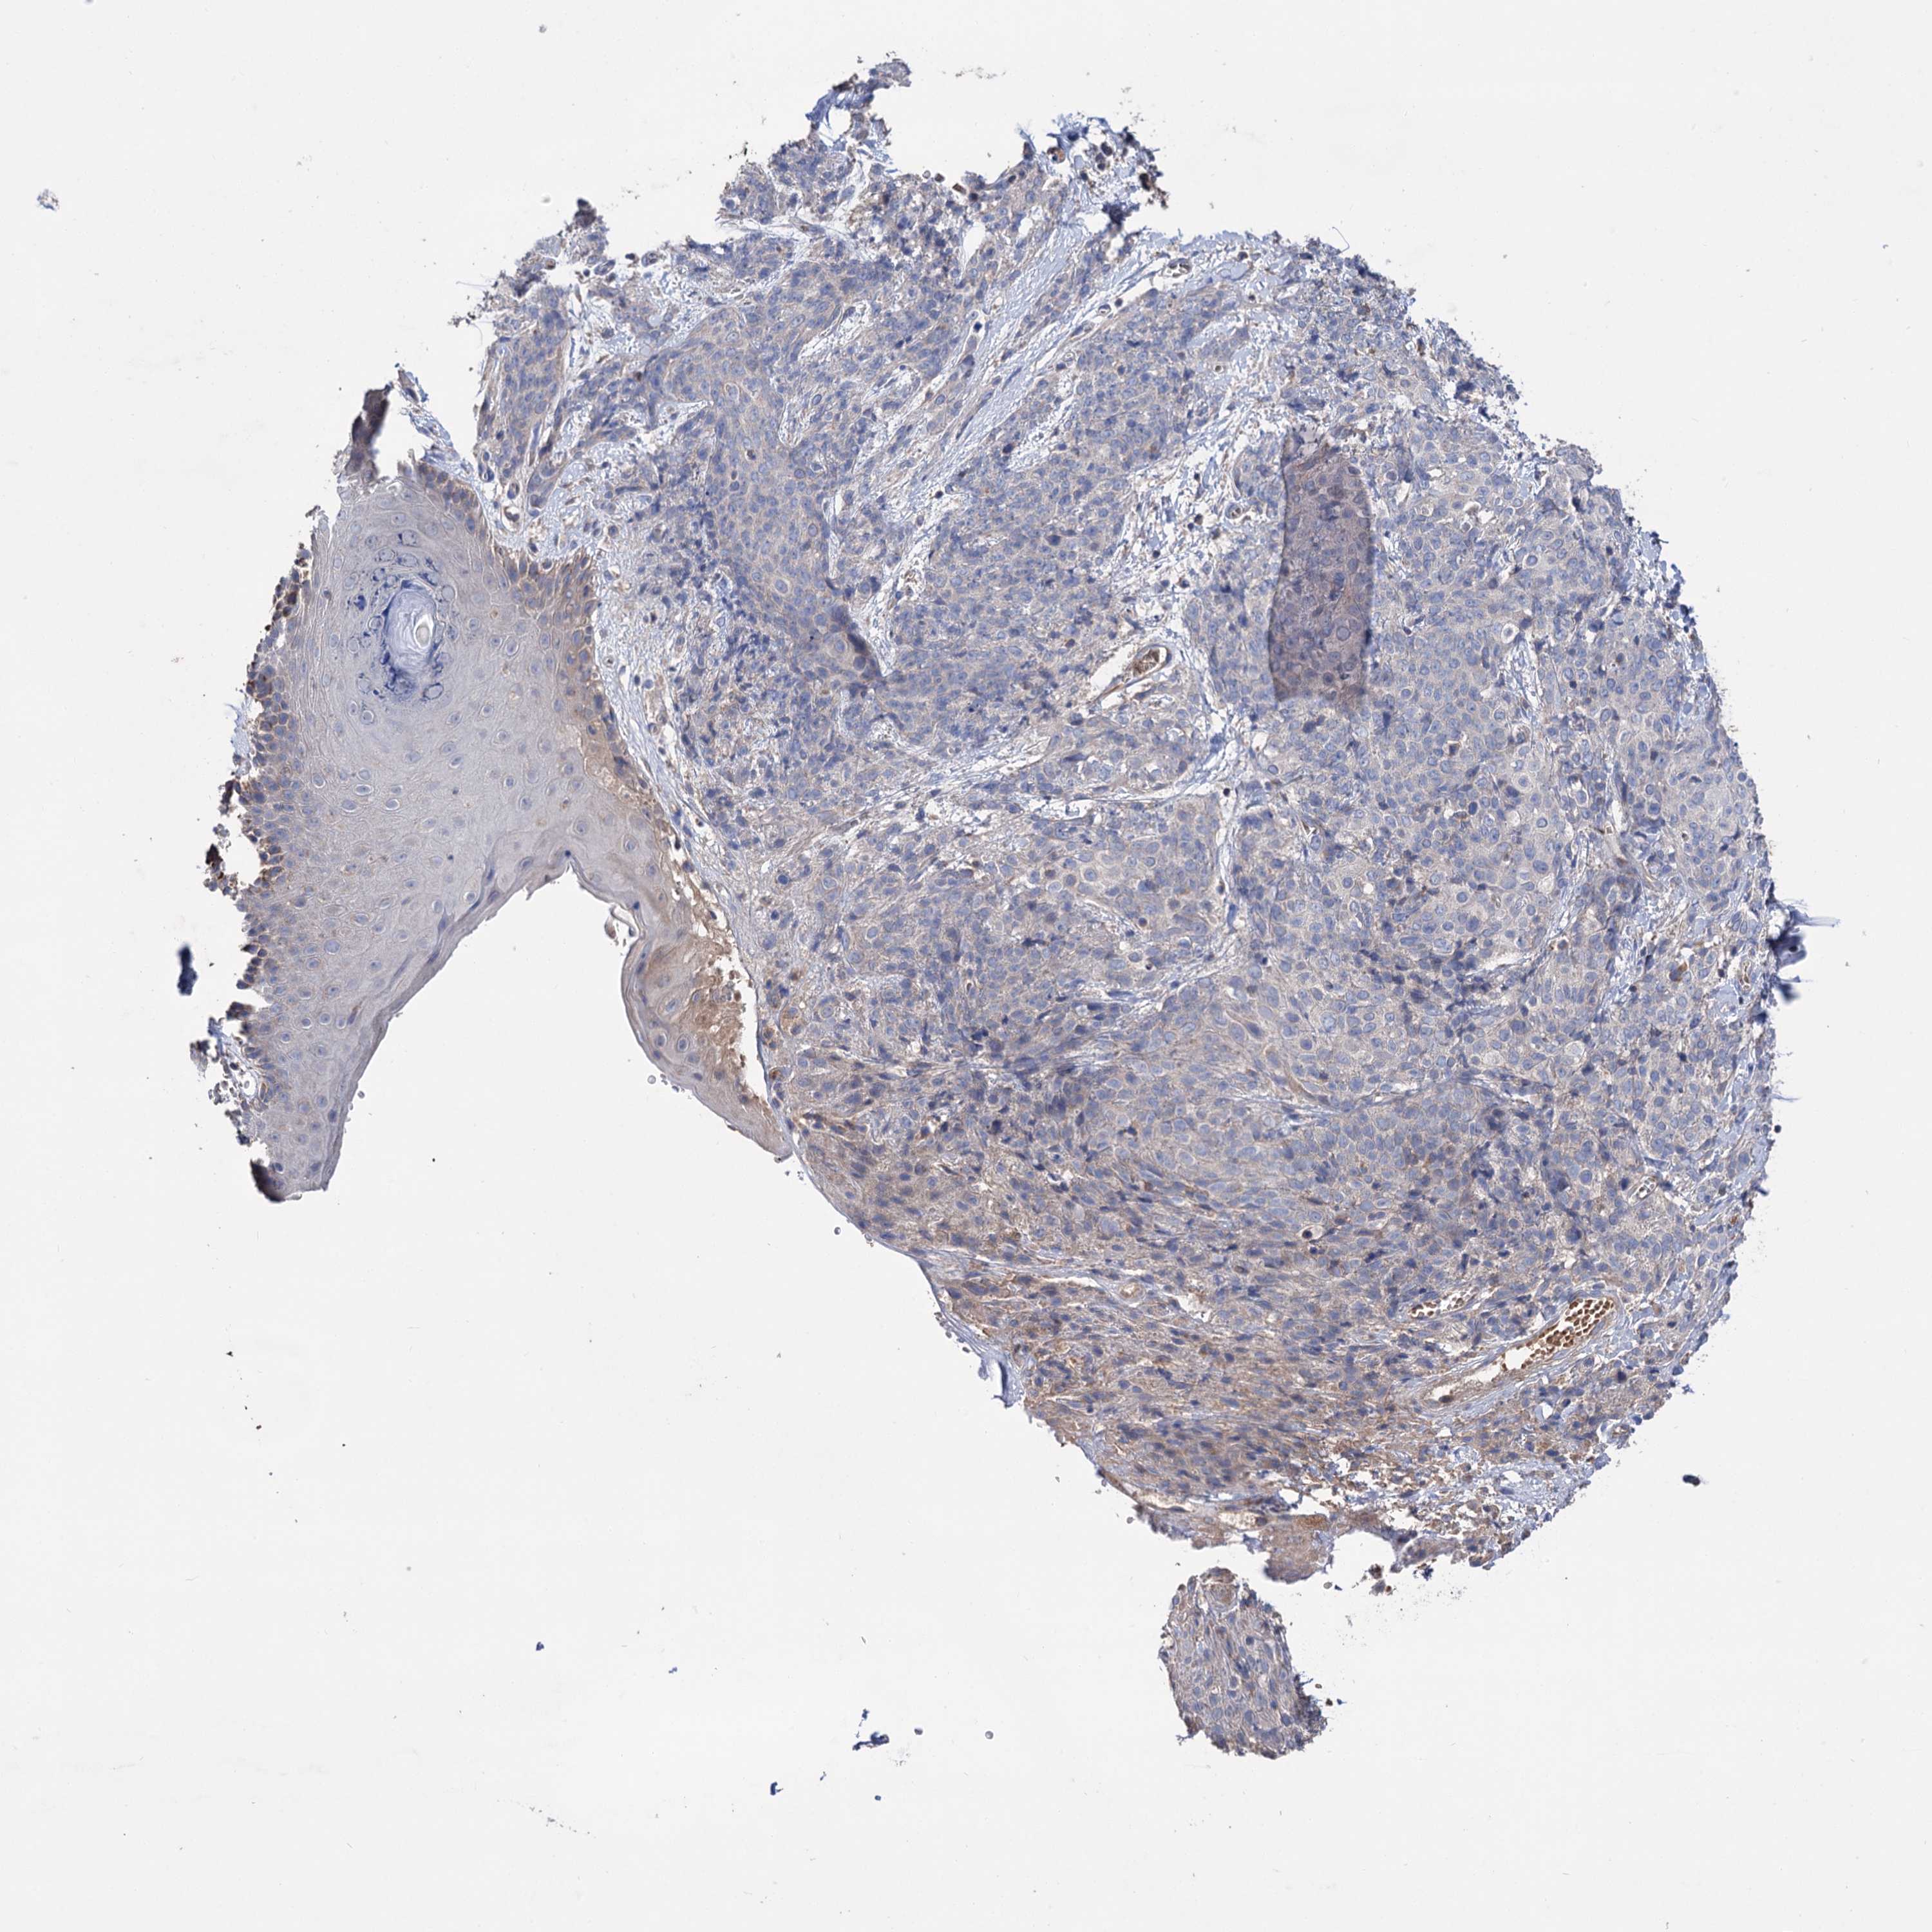

CANCER SKIN CANCER Show tissue menu

SKIN CANCER - Protein expressioni

A mouse-over function shows sample information and annotation data. Click on an image to view it in a full screen mode. Samples can be filtered based on level of antibody staining by selecting one or several of the following categories: high, medium, low and not detected. The assay and annotation is described here.

Each image is clickable and will lead to virtual microscopy that enables deeper exploration of all samples and also displays staining intensity scores, fraction scores and subcellular localization as well as patient and tissue information for each sample.

Antibody HPA039005

Basal cell carcinoma